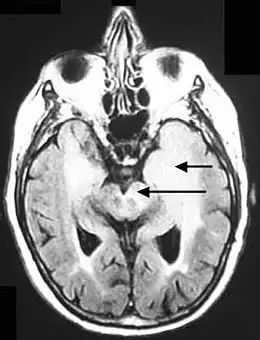

Les conférences de consensus d'anatomopathologistes réunies par l'Organisation mondiale de la santé (OMS) retiennent comme définition d'une gliomatose cérébrale l'infiltration néoplasique diffuse de la glie d'au moins trois lobes cérébraux, impliquant les deux hémisphères ou la matière grise plus profonde[6],[7],[8].